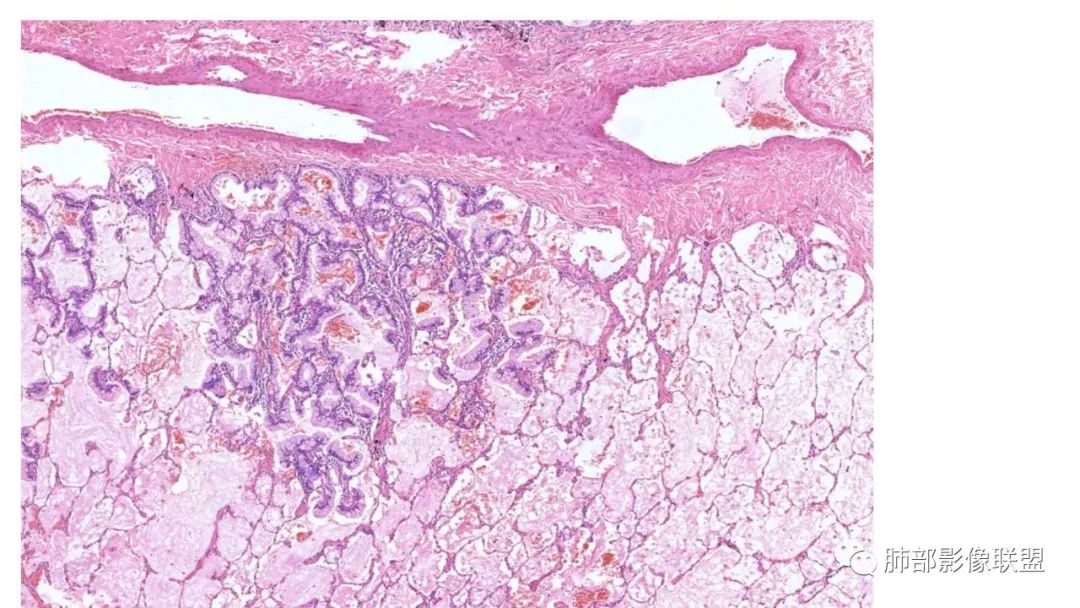

粘液腺癌影像上分为:结节型及斑片型/混合(肺炎型)。

一、结节型粘液腺癌和普通腺癌类似,重视体检及复查不易遗漏

1.多位于胸膜下,90%位于胸膜下,70%下叶胸膜下(125例)

2.病变周围GGO,边界清楚或稍模糊。圆圈征、草帽征、树上蘑菇征等。

3.结节型发展缓慢,淋巴结转移少见。

4.无明显强化或低强化。